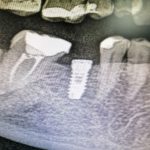

Pasados los tres meses de integración, dimos por finalizado el caso clínico con la colocación de una muela que, en este caso, va atornillada al implante dental mosteo-integrado en el hueso del maxilar inferior. Un caso real de un paciente que nos ayuda a entender cómo proceder ante situaciones, actuales o pasadas, en las que se ha perdido alguna pieza dental.